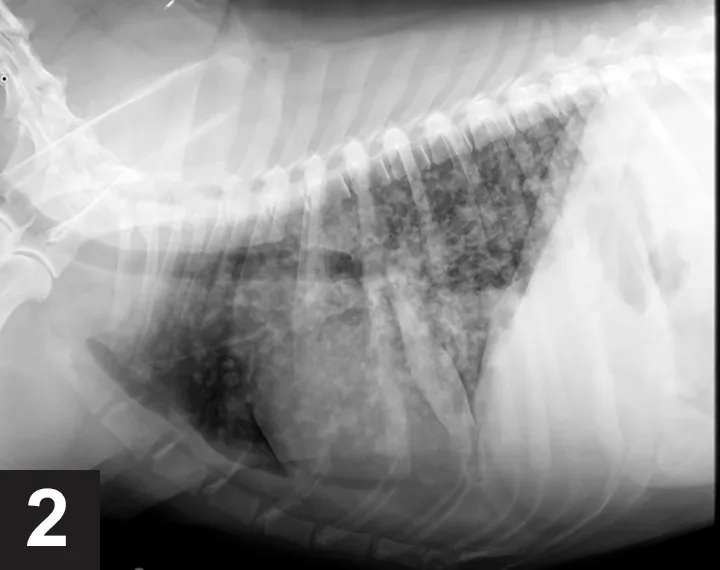

Cytology results were suggestive of blastomycosis based on the presence of abundant budding yeasts with a broad base (Figure 1). On further consultation, the owner revealed that Sadie regularly accompanies her on camping trips to an area near Georgian Bay, Ontario, where blastomycosis is endemic.

FIGURE 1

Blastomyces dermatitidis from a liver aspirate in a dog with blastomycosis. Note the typical budding yeasts. Image courtesy of Centers for Disease Control and Prevention—National Center for Zoonotic, Vector-Borne, and Enteric Diseases; Division of Foodborne, Bacterial and Mycotic Disease